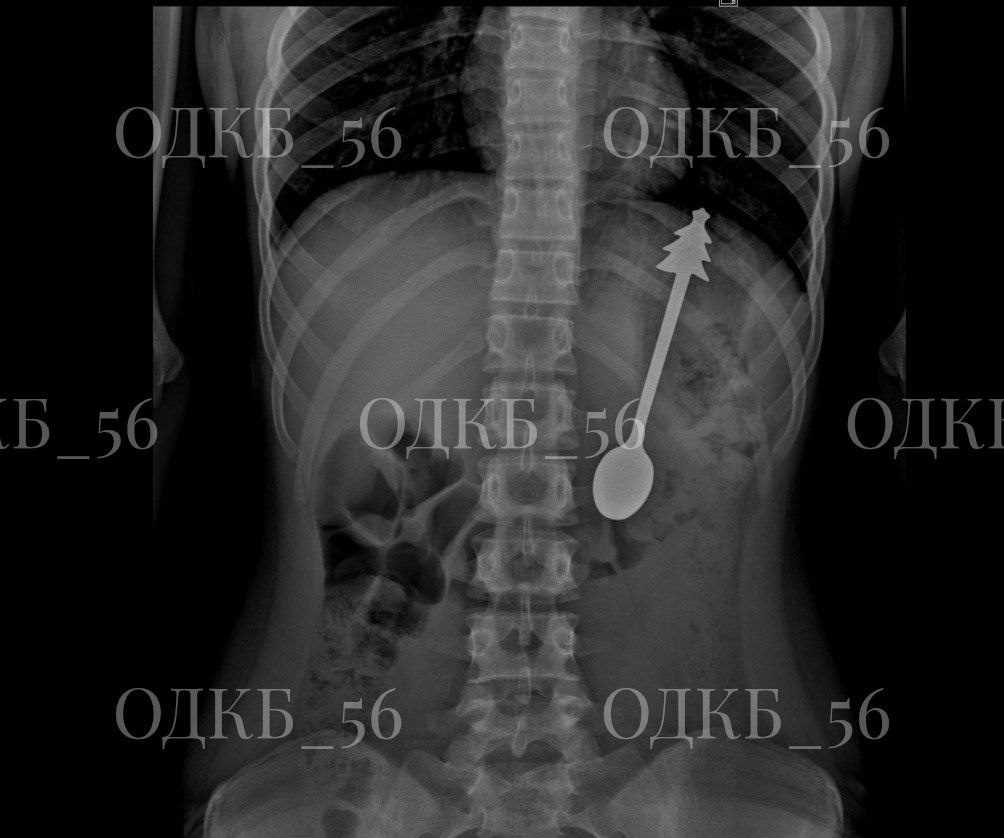

Рентген показал, что инородный предмет находится в желудке. Ребенка госпитализировали в детское хирургическое отделение, где было принято решение о проведении эндоскопического вмешательства.

Ложка, которую достали из ребенка. Фото: ОДКБ